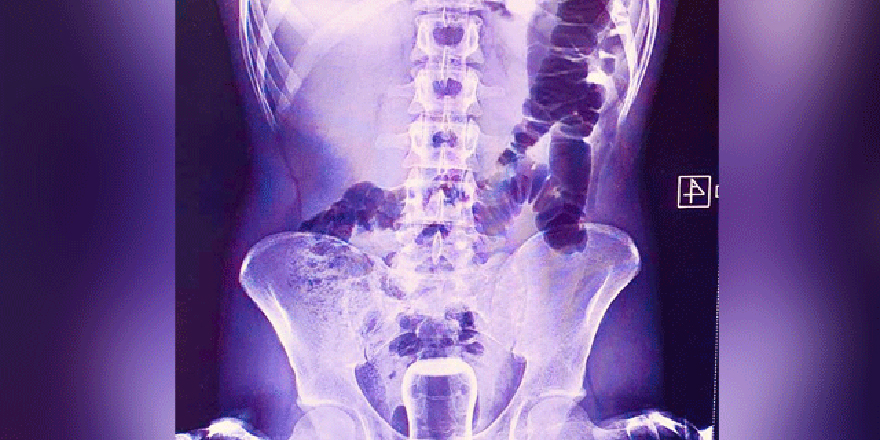

Geçen cuma günü ismi açıklanmayan bir kişi Mehmet Akif İnan Eğitim ve Araştırma Hastanesi'ne başvurdu. Acil serviste hastanın çekilen röntgeninde anüs bölgesinde çay bardağı görüldü.

Bu kişi genel cerrahi servisinde ameliyata alındı. Çay bardağı, uzman doktorlar tarafından gerçekleştirilen operasyonla çıkarıldı.

Ameliyatla sancıdan kurtulup eski sağlığına kavuşan hasta doktorlara, uzun zamandır basur hastası olduğunu, hacamatçıya gittiğini ve yağlı çay bardağın kazayla anüs bölgesine kaçtığını ileri sürerek, ameliyattan dolayı teşekkür etti. (DHA)